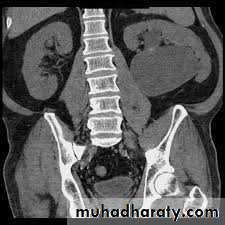

CTTreatment

DefinitionMGU is a nonspecific term implying a spectrum of anomalies associated with pathologically excessive ureteral diameter

Children up to 12 year-ureteral width>7mm

Older children ureteral width>10mm